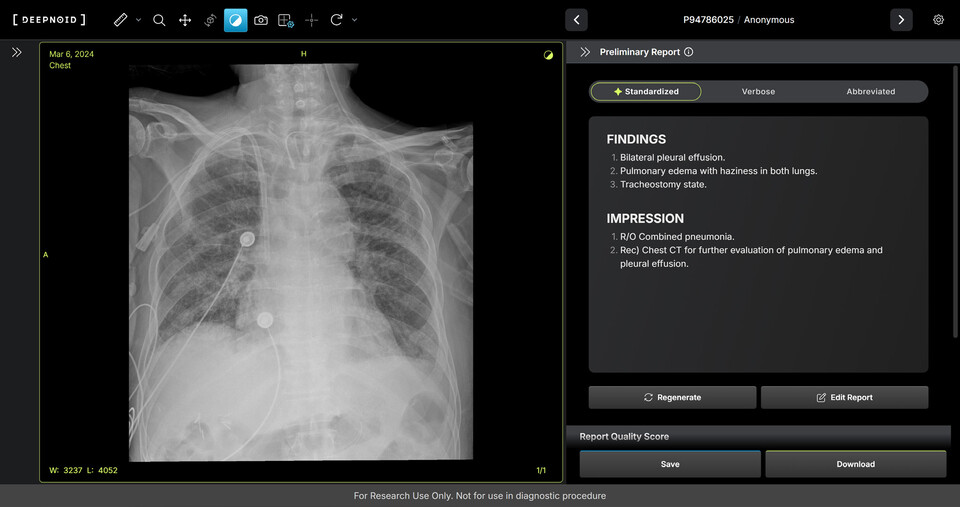

M4CXR은 흉부 X-ray 영상에서 41종의 병변을 판독해 수초 만에 일관성 있고 신뢰성 높은 판독소견서 초안을 작성한다. 이는 흉부 X-ray 영상과 대응되는 1000만 건 이상의 판독소견서 데이터를 학습해 구현된 기술로 특히 응급상황에서 의료진이 즉시 예비 판독 결과를 받을 수 있어 중요한 임상 결정과 환자 진료에 더욱 집중할 수 있도록 지원하며 영상의학과 전문의의 판독을 보조한다.